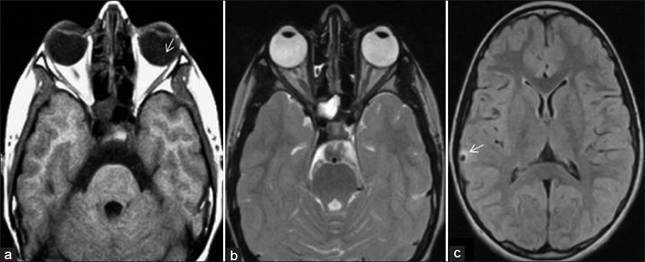

Hình 14

Biểu hiện bệnh ở mắt do ấu trùng sán lợn là khu trú nhiều trên mắt, đa số chỉ có 1 mắt độc nhất, thường gặp nhất là ấu trùng sán nội nhãn. Khu trú hốc mắt ít gặp, nếu có ấu trùng sán xuất hiện dưới dạng một u nông căng mộng, tròn hay bầu dục, u di động, xuất hiện đồng thời với tình trạng viêm cấp. Nếu khu trú ở kết mạc, dưới hình thức một nanghình tròn, phần lớn các nang này nằm ở cùng đồ hay ở góc trong của mắt, thường kèm nhiễm khuẩn, nang sẽ tiến triển thành một abces dưới kết mạc. Tiền phòng có ấu trùng dưới dạng một túi màu trắng nhạt, trong mờ, đôi lúc ở bề mặt của nó có một chấm trắng (đầu của ấu trùng); ở thành của túi có những nhu động biểu hiện hoạt động của ấu trùng, phần lớn các ca như thế thì ký sinh trùng cố định vào mống mắt, nhưng cũng có khi tự nó trôi tự do trong tiền phòng.

Hình 15

Trong dịch kính, ấu trùng sán dưới dạng một túi tròn, trắng nhạt, đục mờ, có bờ óng ánh màu xanh ngả vàng. Phần lớn các ca bệnh, ấu trùng ở thể tự do di động trong dịch kính và dịch kính bị viêm thứ phát. Đáy mắtcó ấu trùng sán dưới dạng một u nang dưới võng mạchình tròn hay hình bầu dục, màu xám nhạt hay xanh lục nhạt, có đường viền rõ nét. Đôi khi nang sán phập phồng như đang thở. Cũng có trường hợp người ta thấy được đầu sán dưới dạng một chấm trắng đục. ngoài nang sán, đôi khi còn có thể phát có bong võng mạc thứ phát.